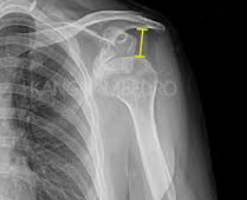

어깨탈구는 일상생활에서 누구나 경험할 수 있는 흔한 부상 중 하나입니다. 이는 어깨 관절이 정상적인 위치에서 벗어나는 상태를 말하며, 갑작스러운 충격이나 부적절한 움직임으로 인해 발생할 수 있습니다. 증상으로는 심한 통증, 움직임의 제한, 팔의 변형 등이 있으며, 경우에 따라서는 신경 손상이나 혈관 손상을 동반하기도 합니다. 치료 방법은 탈구의 정도와 환자의 상태에 따라 달라지지만, 일반적으로는 관절을 원래 위치로 복원하는 정복술과 통증 관리, 그리고 재활 운동이 포함됩니다. 이 글에서는 어깨탈구의 증상을 인식하는 방법과 효과적인 치료 접근법에 대해 자세히 알아보겠습니다. 오늘은 어깨탈구 증상 및 치료방법에 대해 알아보겠습니다.

어깨탈구는 어깨 관절이 정상적인 위치에서 벗어나는 상태를 말합니다. 이는 갑작스러운 충격이나 부상으로 인해 발생할 수 있으며, 심한 통증과 함께 어깨의 움직임이 제한됩니다. 증상으로는 어깨의 변형, 팔을 움직일 때의 고통, 그리고 팔의 힘이 약해지는 것 등이 있습니다. 치료 방법은 탈구의 정도와 환자의 상태에 따라 달라지지만, 일반적으로는 물리치료, 슬링 착용, 때로는 수술이 필요할 수도 있습니다. 이 글에서는 어깨탈구의 증상을 자세히 알아보고, 효과적인 치료 방법에 대해 탐구해보겠습니다. 어깨탈구의 이해를 통해, 이러한 부상을 예방하고, 만약 발생했을 때 적절히 대처하는 방법을 배울 수 있을 것입니다.